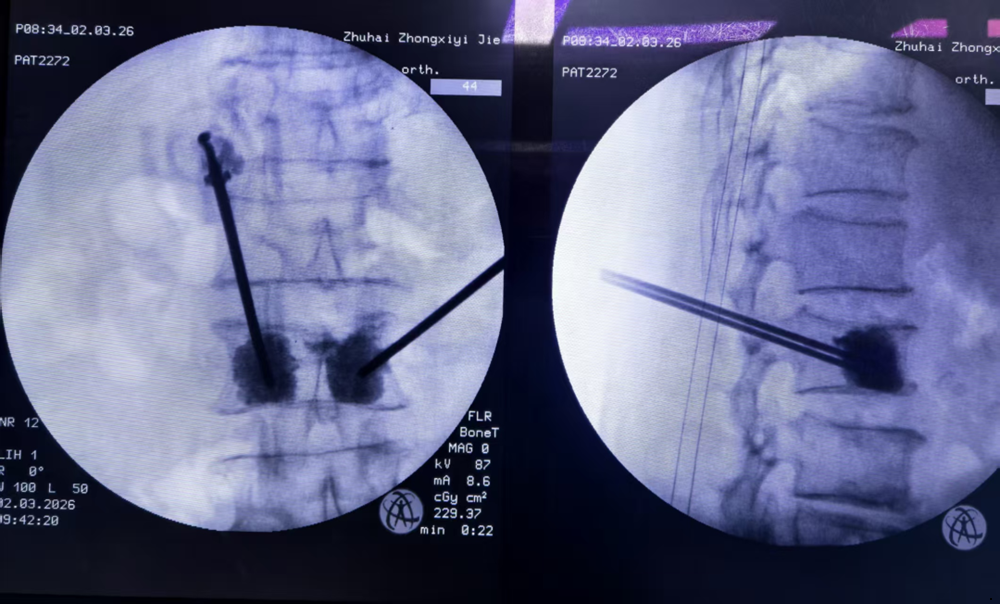

图1:脊柱骨科毛吉刚主任在C型臂引导下进行椎体成形术操作,麻醉科方剑主任保驾护航。

由于采用侧卧位而不是俯卧位,手术中心率、血氧、血压、呼吸各项指标都保持得很平稳。手术在半小时左右顺利完成,C臂X光机透视显示“骨水泥”在骨折的腰椎里“顶天立地”,疼痛也立即得到了明显缓解。

图3:C型臂透视显示穿刺针位置和骨水泥注入情况

经皮椎体成形术(Percutaneous Vertebroplasty, PVP)和椎体后凸成形术(PKP)是目前治疗骨质疏松性椎体压缩骨折的“金标准”微创手术。手术在局部麻醉下进行,通过C型臂X光机引导,仅需背部2.5毫米左右的微小切口,将穿刺针精准置入骨折椎体,注入骨水泥,即可迅速稳定骨折、缓解疼痛。